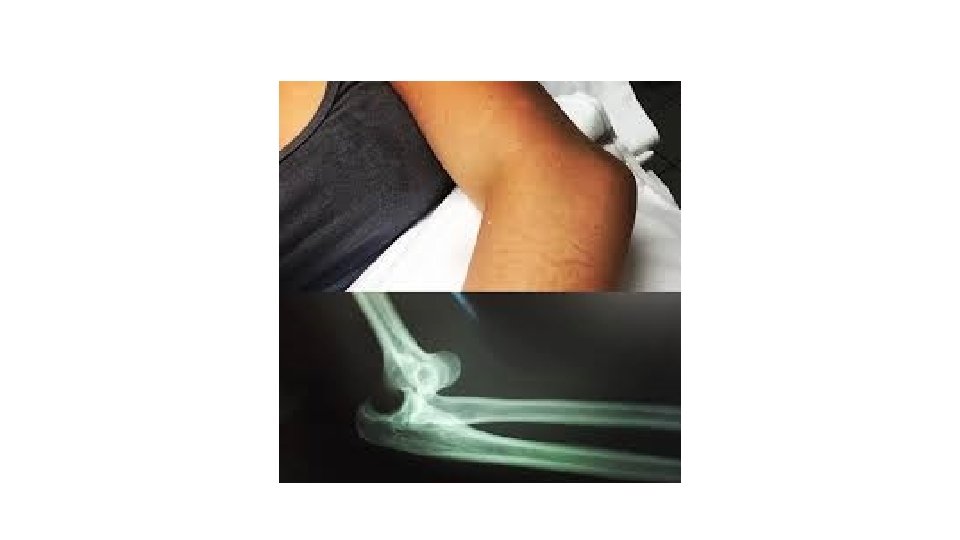

Luxation • La luxation est une déchirure des ligaments (donc entorse) avec en plus

Luxation • La luxation est une déchirure des ligaments (donc entorse) avec en plus l'articulation déboitée. C'est la perte des rapports articulaires normaux • Il s’agit toujours d’une urgence chirurgicale

Clinique • Déformation • Douleur • Impotence totale

Gestes • Ablation bagues et bijoux – A JEUN • Examen NEURO-VASCULAIRE et CUTANE

Gestes • Ablation bagues et bijoux – A JEUN • Examen NEURO-VASCULAIRE et CUTANE = recherche signes de gravité immédiate (ouverture/ischémie) • Immobilisation • Examen complémentaire • Avis chirurgical